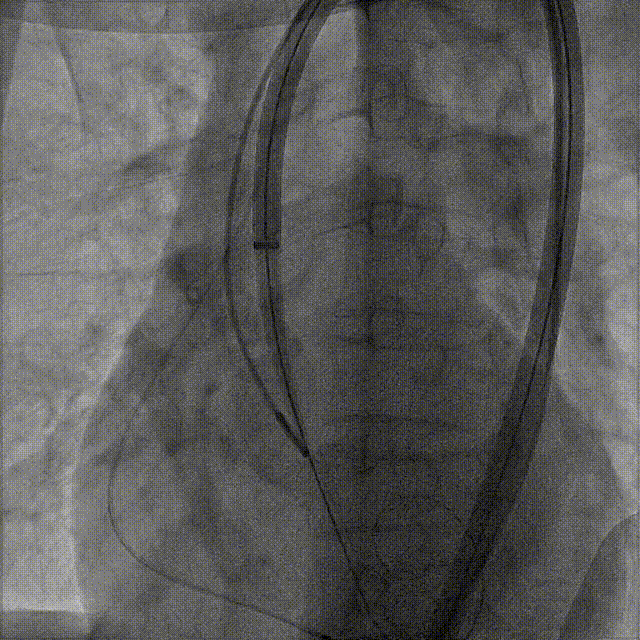

右窦中心造影

大鞘到STJ

瓣膜调弯后解离

瓣膜右窦中心调整

定位键窦不对齐

灵活旋转操作

确认窦对齐